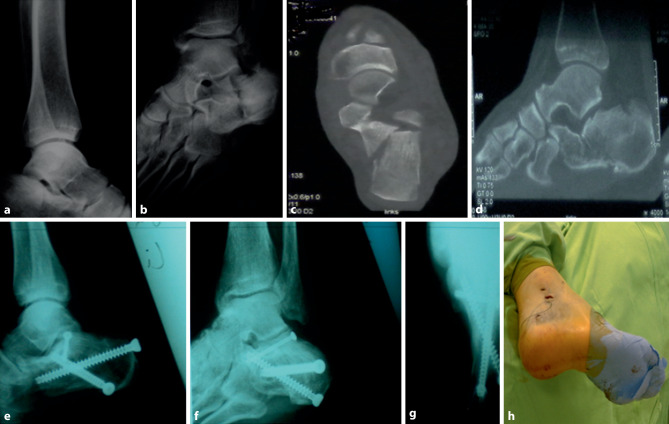

Background: Displaced intra-articular calcaneal fractures are a complication-ridden injury to treat and there are various treatment techniques to address this injury. The aim of this study was to evaluate the mid-term outcome of a percutaneous two-point distractor technique in patients with displaced intra-articular calcaneal fractures.

Methods: A retrospective data analysis of patients with intra-articular calcaneal fractures treated in a level 1 trauma center was conducted. The patients were subsequently invited for a follow-up visit to assess the mid-term outcome. The Böhler's and Gissane's angles, the American Orthopaedic Foot & Ankle Society hindfoot score, the Maryland foot score and a visual analog scale for pain were measured preoperatively and postoperatively and after at least 6 years to assess the radiological and functional outcome.

Results: Of the patients 59 completed the study with a mean follow-up of 76 months after surgery. The mean American Orthopedic Foot and Ankle Society hindfoot score at the last follow-up visit was 81, the mean Maryland foot score was 78. There were three cases (5%) of superficial wound complications and secondary arthrodesis of the subtalar joint was performed in five patients (8%).

Conclusion: The low rates of postoperative infections and secondary arthrodesis in this study underline the good to excellent mid-term functional results for a minimally invasive technique.

背景:移位的跟骨关节内骨折是一种并发症缠身的损伤治疗,有各种治疗技术来解决这种损伤。本研究的目的是评估经皮两点牵引器技术在移位的跟骨关节内骨折患者中的中期疗效。方法:回顾性分析在某一级创伤中心治疗的跟骨关节内骨折患者的资料。随后邀请患者进行随访以评估中期结果。术前、术后及至少6年后分别测量Böhler's和Gissane's角度、美国骨科足踝协会后足评分、马里兰足评分和视觉模拟疼痛量表,以评估放射学和功能预后。结果:59例患者完成研究,术后平均随访76个月。最后一次随访时,美国骨科足踝协会的平均后足评分为81分,马里兰州的平均后足评分为78分。有3例(5%)出现浅表创面并发症,5例(8%)行距下关节继发性关节融合术。结论:在本研究中,低发生率的术后感染和继发性关节融合术强调了微创技术良好到优异的中期功能效果。